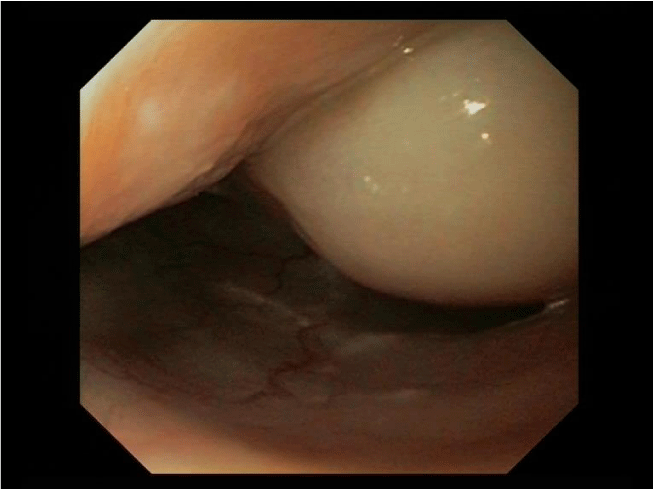

On flexible esophagogastroduodenoscopy, a large partially pedunculated submucosal soft tissue tumour, whitish-yellow in color, commencing at the proximal esophageal sphincter, and continuing down to the distal esophagus (Figure 1) was found. Flexible bronchoscopy revealed the proximal border of the tumour infiltrating both aryepiglottic folds (Figure 2) and a tracheal compression resulting in a tracheal stenosis of 30%. The right upper lobe bronchus appeared compressed with mucosal inflammation. However, the mucosa was not affected. Cytological examination of the bronchoalveolar lavage and repeated biopsies by flexible endoscopy failed to determine the diagnosis. Therefore, three consecutive rigid hypopharyngo-, microlaryngo- and esophagoscopies with multiple deep biopsies in different locations (hypopharynx, aryepiglottic folds and proximal esophagus) containing a total volume of more than 5 cc were performed. Pathological examination of these biopsies revealed a myxoid lesion, possibly a myxoid liposarcoma.

Figure 1: Esophagoscopic view: Submucosal soft tissue tumour of whitish-yellow color of the esophagus.